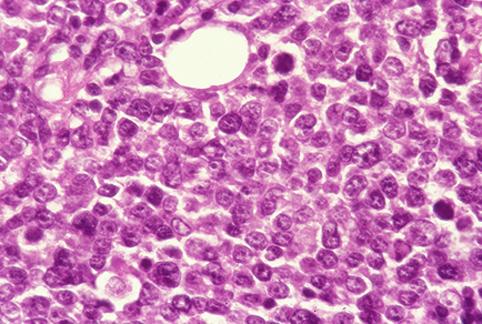

A case of so-called early gastric malignant lymphoma which characteristically showed various features.

Malignant Lymphoma/Malignant lymphoma

submucosa